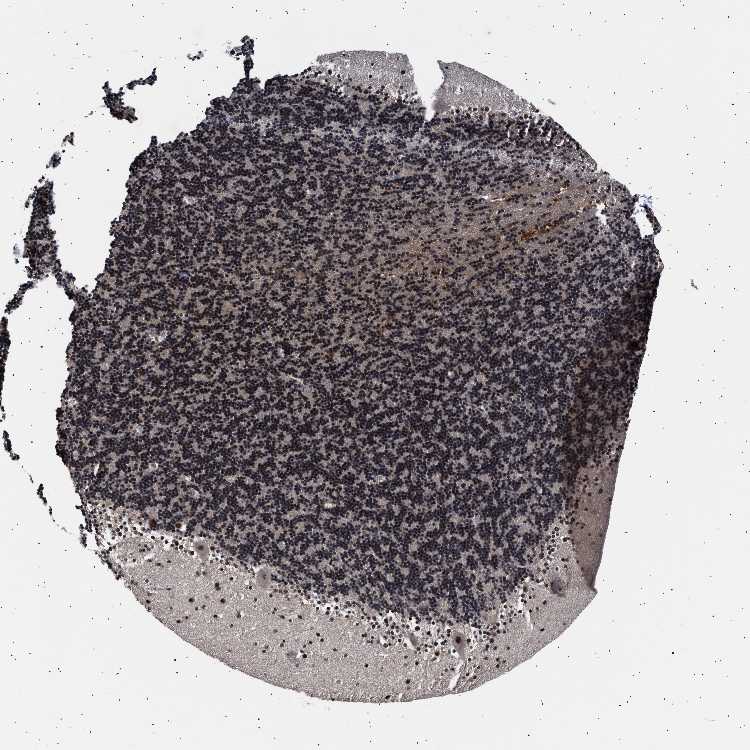

CEREBELLUM - Antibody stainingi

Antibody staining in the annotated cell types in the current human tissue is reported as not detected, low, medium, or high, based on conventional immunohistochemistry profiling in selected tissues. This score is based on the combination of the staining intensity and fraction of stained cells.

Each image is clickable and will lead to virtual microscopy that enables deeper exploration of all samples and also displays staining intensity scores, fraction scores and subcellular localization as well as patient and tissue information for each sample.

Antibody HPA020404Antibody HPA024029Antibody HPA024100

Purkinje cells HighMediumNot detected

Cells in granular layer HighLowNot detected

Cells in molecular layer HighLowNot detected